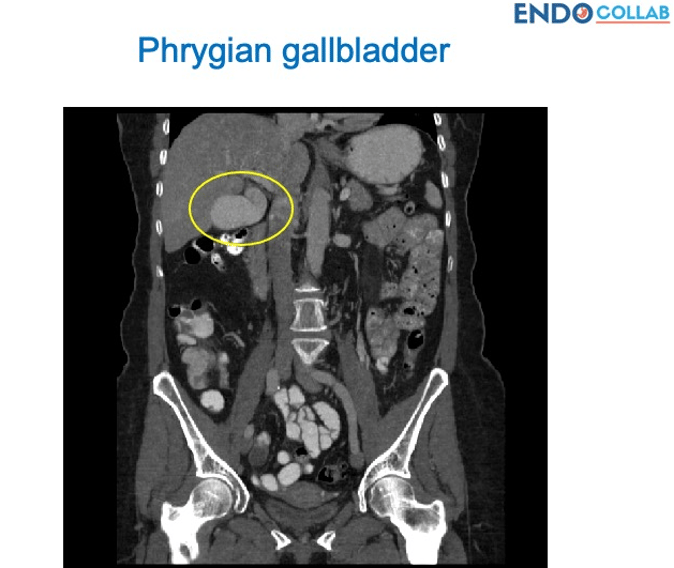

What is a Phrygian (Cap) Gallbladder?

A phrygian cap gallbladder is a congenital anomaly of the gallbladder with an incidence of 4%. It can simulate a mass in the liver during hepatobiliary imaging and is sometimes mistaken for pathology. A Phrygian cap, however, has no pathological significance and normally causes no symptoms.

The gallbladder is a pear-shaped organ measuring about 7 cm long and 3 cm wide and is located on the undersurface of the liver. Variations of the gallbladder include anomalies of form, location or number of gallbladders. A phrygian cap is the most common congenital abnormality of the gallbladder with an incidence of 4%. Although it can simulate a mass in the liver on radiological imaging studies, it does not have any pathological significance, and there is no need for cholecystectomy, unless it causes symptoms such as biliary colic or cholecystitis (1).